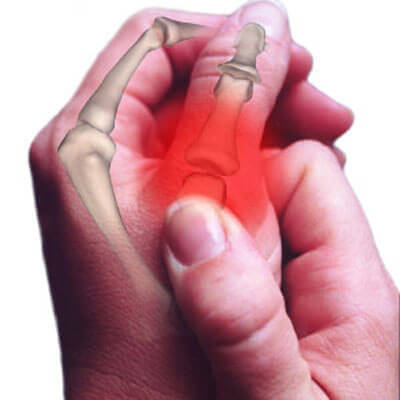

Lyden vi hører når vi knekker fingrene, håndleddene, anklene eller andre kroppsdeler kommer av bobler i leddvæsken. Det er viktig å huske på at leddene er forskjellige deler av skjelettet som møtes og at de er dekket av en tykk væske. Når et fingerledd, for eksempel, blir bøyd eller strukket, så deler leddet seg.

Kapselen rundt leddet strekkes ut og forstørres, slik at trykket faller. Når dette skjer vil de oppløste gassene i væsken danne bobler, som så “eksploderer” og forårsaker den velkjente knekkelyden.

Gassen bruker en halvtime på å oppløses i væsken, så etter å ha knekt et ledd burde du ikke prøve å knekke det igjen de neste 30 minuttene. I forhold til helserisikoen forbundet med denne uvanen finnes det kun en begrenset mengde studier. Forskere har forsøkt å analysere leddene til diverse personer som ofte knekker fingrene og for å observere eventuelle skader, som leddgikt og artrose.

I studien så de tegn på skader i bløtvevet og at personene hadde redusert evne til å gripe objekter. Dette er mest sannsynlig forbundet med raskt og repeterende utstrekking av leddbåndet.